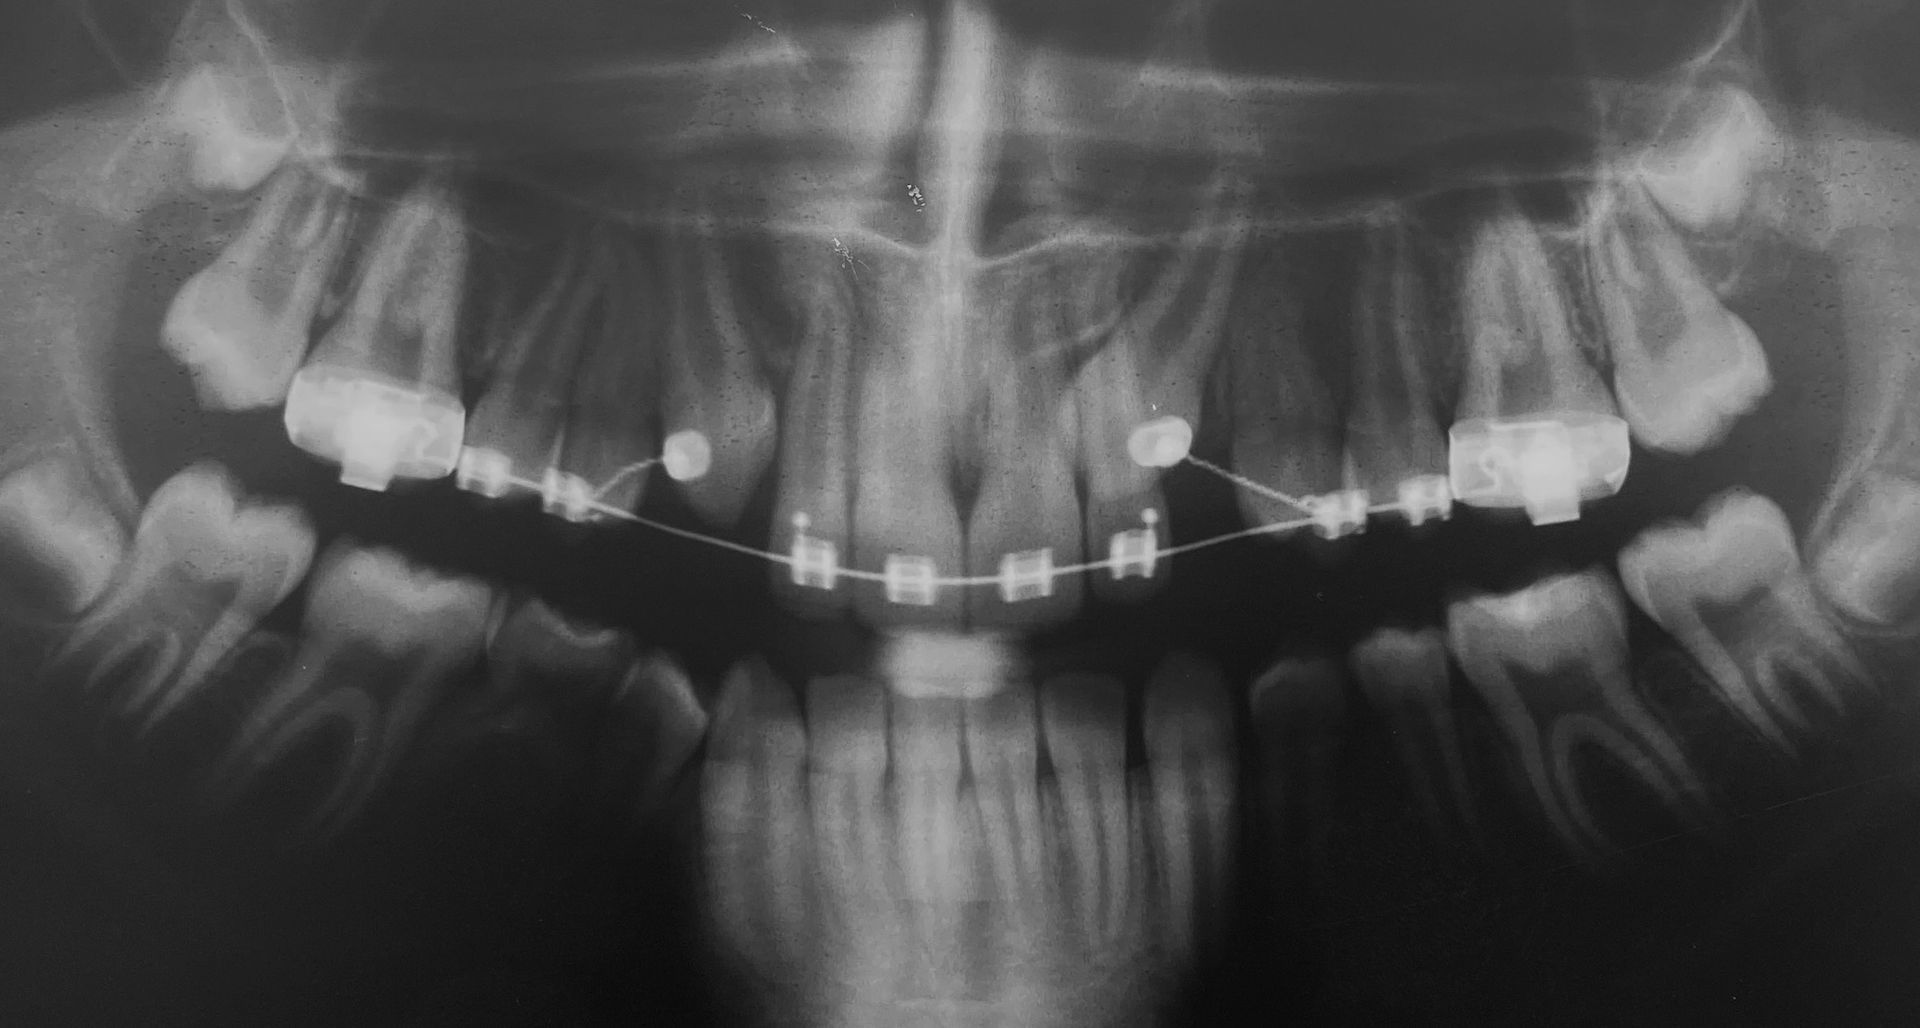

Radiologia digitale 2D e 3D

Tecnologia a bassa emissione di raggi che consente diagnosi dettagliate e sicure. Le immagini digitali ci permettono una pianificazione precisa ed efficace delle cure.